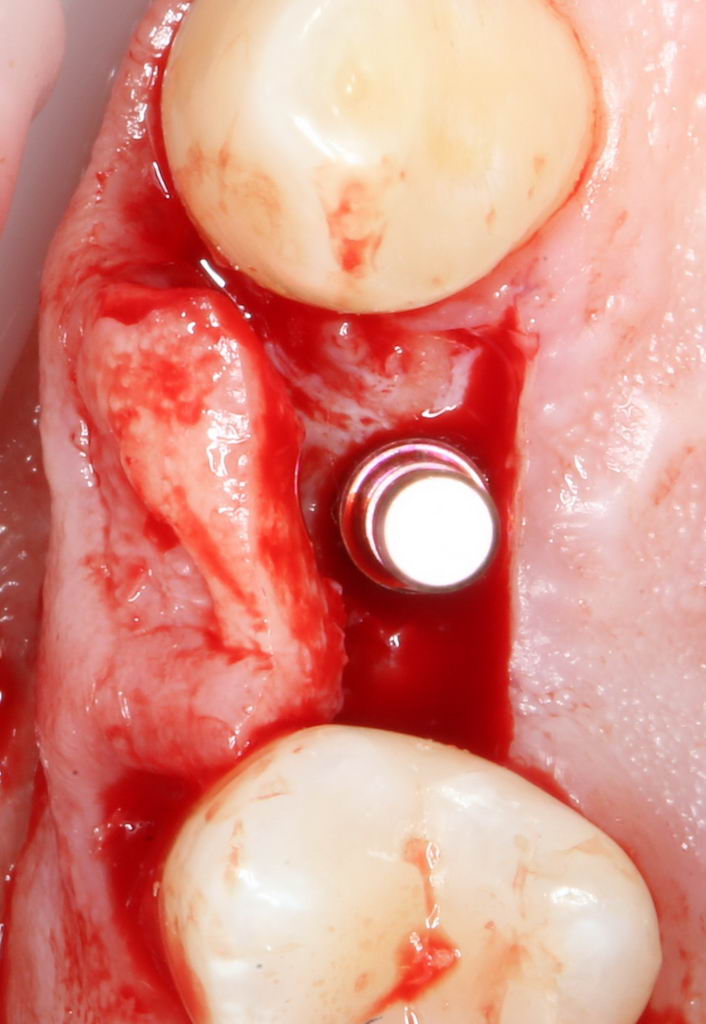

Еще раз проверим положение имплантата:

Учитывая то, что на нём уже установлен временный абатмент TempBase, сделать это очень просто. Фактически, сейчас мы с Вами видим картинку, которую увидит ортопед перед установкой коронки. Это очень удобно.

Больше нам абатмент TempBase не нужен, мы его убираем:

Без абатмента можно оценить позиционирование имплантата по глубине погружения. Напомню, что XiVE — это субгингивальная имплантационная система, поэтому ортопедическая платформа имплантата должна находиться на уровне костной ткани. Что и было выполнено в нашем случае.